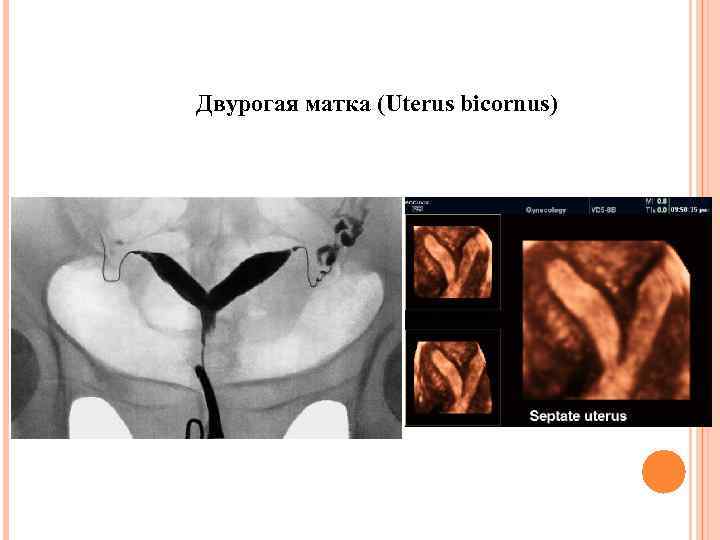

Аномалии развития Мюллеровых протоков Двурогая матка (Uterus bicornus) С одним влагалищем С перегородкой С двумя влагалищами

Аномалии развития Мюллеровых протоков Двурогая матка (Uterus bicornus) С одним влагалищем С перегородкой С двумя влагалищами

Двурогая матка (Uterus bicornus)

Двурогая матка (Uterus bicornus)